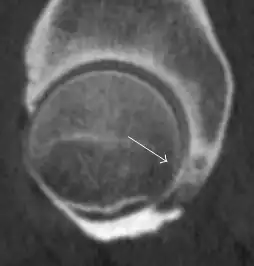

Synovial chondromatosis can be confidently diagnosed by X-ray when calcified cartilaginous chondromas are seen. However, other synovial proliferative processes, such as pigmented villonodular synovitis, require MRI for accurate diagnosis, although noncalcified synovitis can be suspected in radiographs by indirect signs, such as soft tissue swelling and/or erosions in the femoral head, femoral neck, or acetabulum (Figure 7).[1]

Figure 7:

Axial CT image of pigmented villonodular synovitis eroding the posterior cortex of the femoral neck.[1]

Sagittal T2* gradient echo image showing a posterior soft tissue mass with hypointense areas secondary to hemosiderin deposition.[1]

X-ray of synovial chondromatosis.[1]

CT of synovial chondromatosis.[1]

In synovial proliferative disorders, MRI demonstrates synovial hypertrophy. In the case of PVNS, characteristic foci of low signal intensity related to hemosiderin deposition are better seen on gradient echo T2* images (Figure 7). In the case of synovial osteochondromatosis, the synovial hypertrophy is accompanied by intermediate signal cartilaginous loose bodies and/or low signal calcified loose bodies.[1]